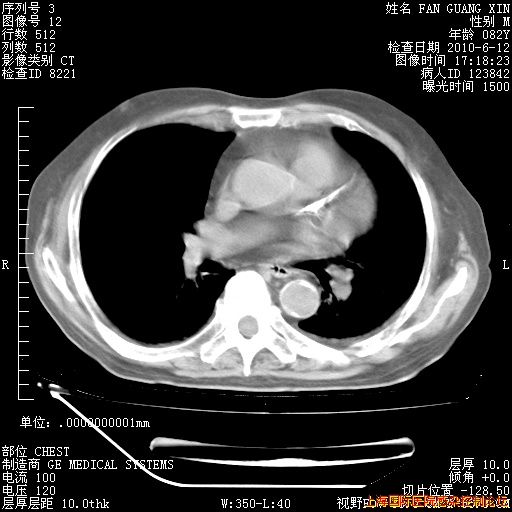

补发6月12日肺部CT肺窗

6月12日肺窗

6月12日纵膈窗